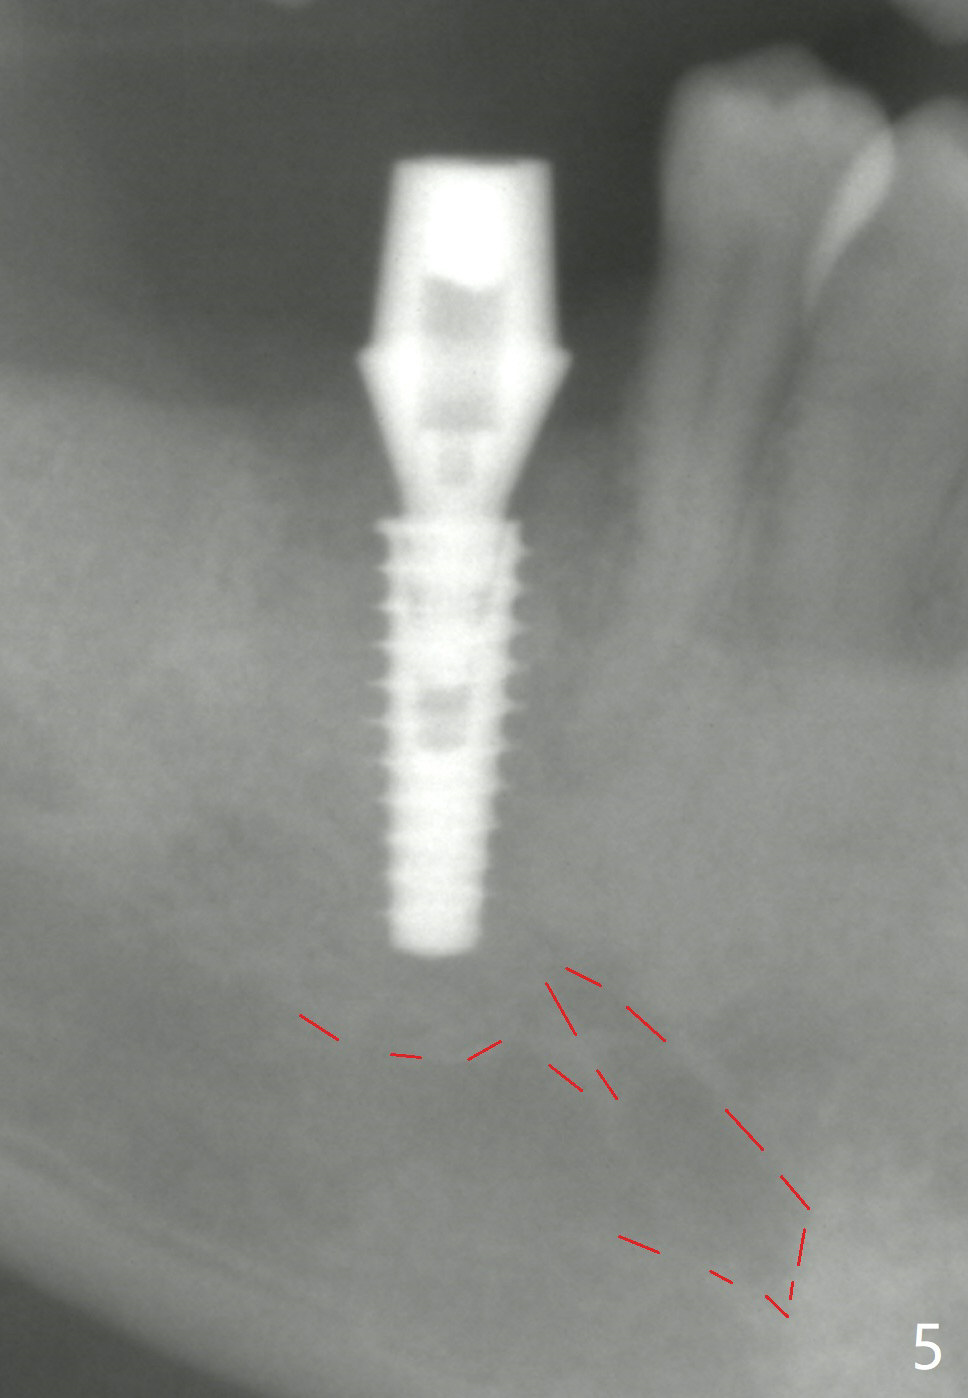

The final implant is placed a little too deep in this case. The problem can be avoided by using Tap with soft tissue depth mark and is solved by using a longer implant (5x13 mm) or having an abutment with longer cuff (5 or 6 mm). Postop there is tooth sensitivity. When the latter disappears, the patient feels the right jaw different. Panoramic X-ray taken 2 months postop shows that the implant has clearance from the Inferior Alveolar Canal (Fig.5 red dashed line).